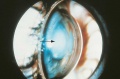

Ectopia lentis. In a case of microspherophakia, the lens (arrow) is trapped anteriorly by the pupil, resulting in iris bombé and a dramatic shallowing of the anterior chamber.